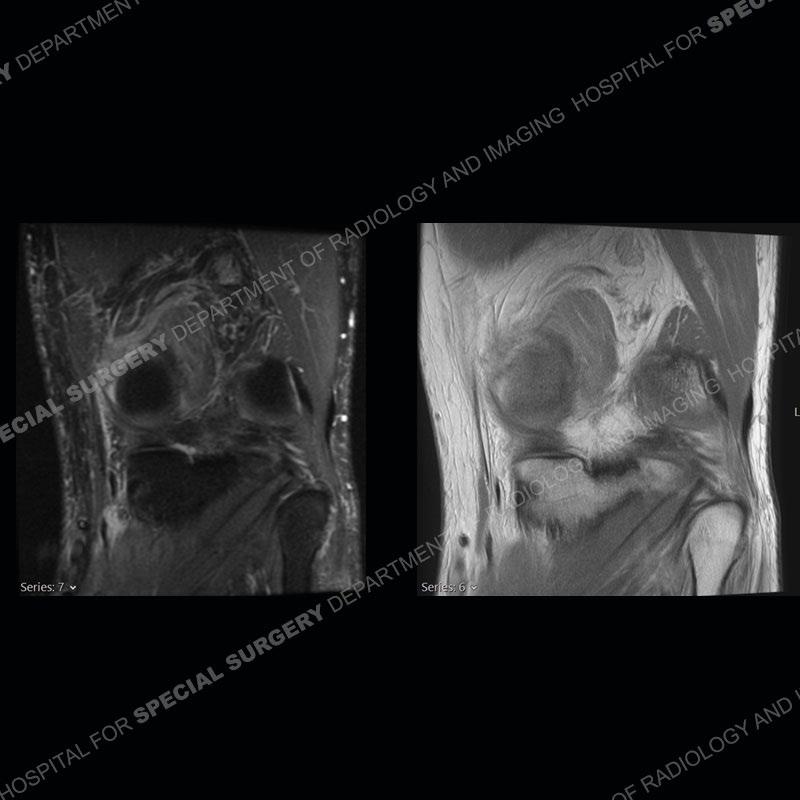

Findings

The radiographs show degenerative change of the medial compartment and a varus knee, but they are not germane to this case. No acute bony injury is present. The MRI shows edema of the posterior medial knee/soft tissue and a focal area of a partially disrupted low signal structure. The details are kept at a minimum in the findings of this case on purpose.

Diagnosis: Partial Disruption Medial Head Gastrocnemius (MHG)

The findings were kept purposefully vague as identifying the structures early on takes away a lot of the diagnosis. An uncommon entity and one of which we do not see a lot. Enthesopathic changes and tendinosis are seen as are distal MHG injuries, but proximal tears are rarely present. This case highlights a number of points. One, it almost always comes down to anatomy. Perhaps not a structure we normally spend too much time on, except save for diagnosing a Baker’s cyst, but knowing where this structure and all structures exist in all three planes is imperative. Second, when you think you are making a “call” or finding that you have never made before, step back and think is this just the abnormal presentation of a common pathology. That situation arises much more frequently. Third, if you look at it once, twice, and probably a third time and are confident in your odd or very rare diagnosis, stick to your guns. Especially, when it comes down to anatomic structures, the proof will be in the images.

Fourth, use all imaging planes and different pulse sequences to make your diagnosis. The edema highlighted in this case can be seen as the obscuration of fat on the PD images but is much easier to perceive as the high signal on the IR pulse sequences. The actual disruption of the MHG myotendinous junction is only able to be seen on the axial images. On the sagittal and coronal images, we get a sense something is wrong but hard to be exact. Lastly, when you look at a study and something just seems off (as I would say the sagittal and coronal images do with that dark band of tissue posteriorly), listen to yourself and go through the study slowly and meticulously. Most of the time you will find you were right, and something indeed is present.